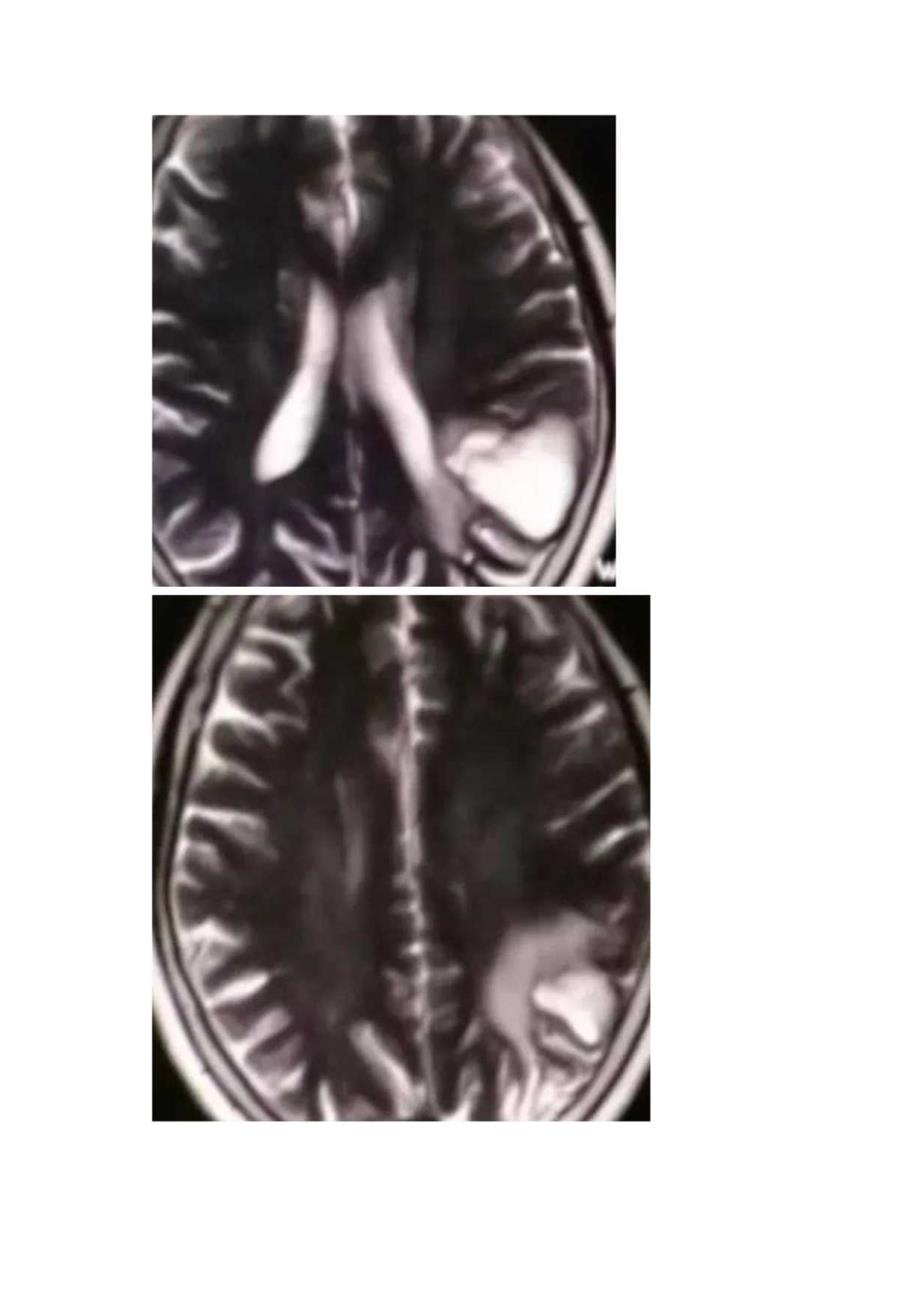

脑淀粉样血管病影像征象